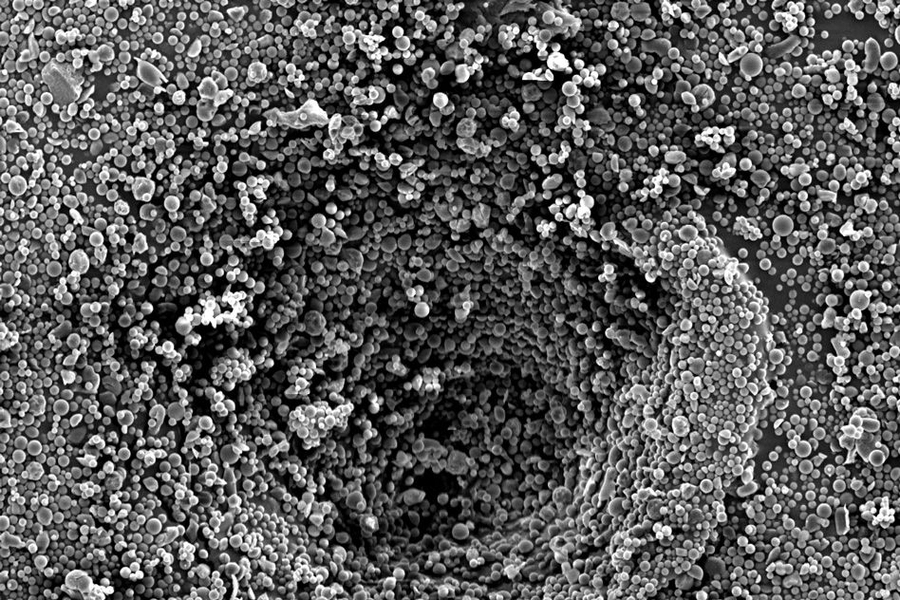

Researchers at MIT, BWH, and MGH have developed a strategy that enables point-of-care personalized therapy for glioma patients. Shown here is an electron microscopy image of the drug-delivery system developed by this team.

Caption: Researchers at MIT, BWH, and MGH have developed a strategy that enables point-of-care personalized therapy for glioma patients. Shown here is an electron microscopy image of the drug-delivery system developed by this team.

To deliver the drugs locally, the researchers developed microparticles in which the NAMPT inhibitor is embedded in PLGA, a polymer that has been shown to be safe for use in humans. Another desirable feature of PLGA is that the rate at which the drug is released can be controlled by altering the ratio of the two polymers that make up PLGA — lactic acid and glycolic acid.